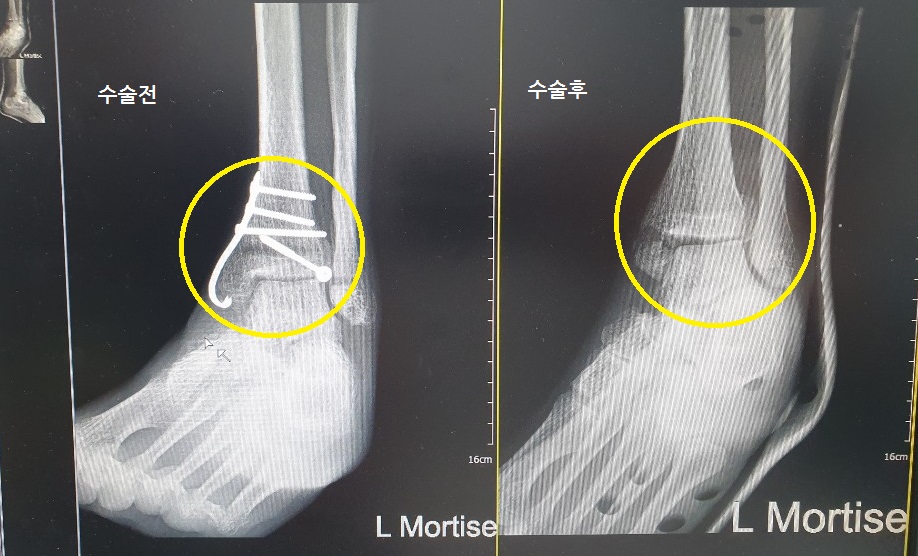

이렇게 일상을 즐기다가, 병원에 3개월 만에 갔었다.

자유롭게 걸어다닐 때였는데 이제 핀을 다 뽑자고 하신다.

설날에 쉬기위해 설 전날로 수술을 잡았다.

그리하여 1월 20일 입원!

사고 발생 7개월만이다.

수술 후

비용은 총 30만원 가량 나왔다.

수술 통증은 별로 없었는데,

이건 개인차가 있는듯 하다.

핀삽입 수술때도 나는 무통주사를 한번도 눌러본적이 없어서..

참고로 전신 마취로 진행했다.